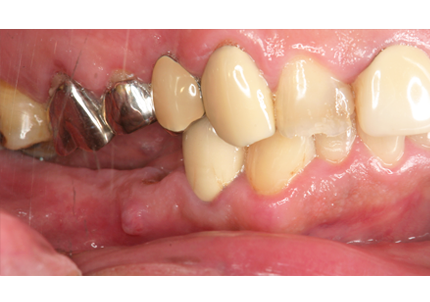

1.初診時口腔内写真(2014年6月)

2.治療終了(2016年6月)

・上顎補綴物再製

・右下2本インプラント

・左下ジルコニアクラウンブリッジ